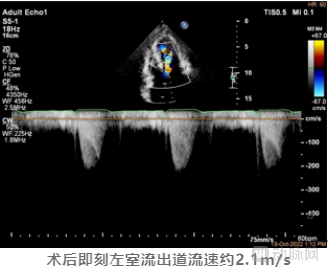

术后彩超提示SAM征消失,二尖瓣反流改善,LVOT收缩期流速由术前6.1m/s降低至术后2.1m/s,左室流出道峰值压差更是从术前的150mmHg下降至17mmHg,术中即刻消融效果使得流出道压差减小量高达133mmHg。